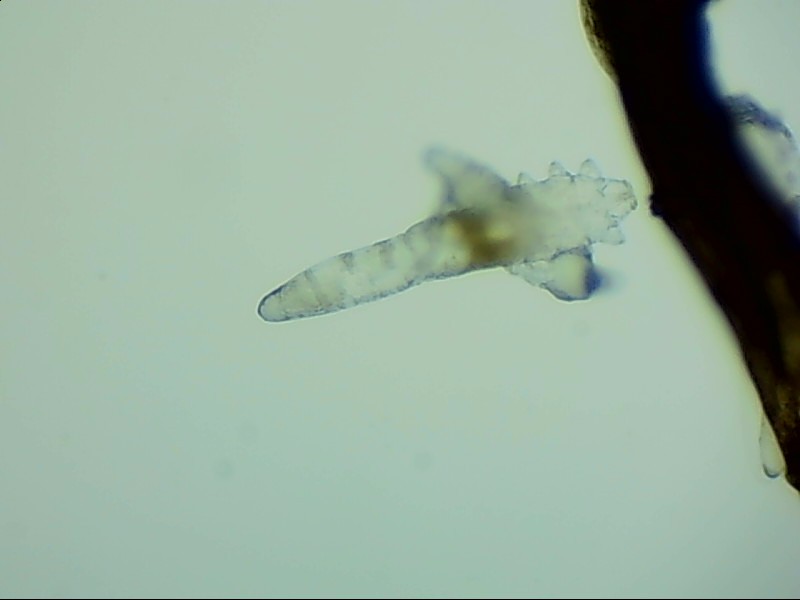

螨蟲無所遁形,螨蟲鏡檢:

螨蟲鏡檢主要是通過顯微鏡觀察,它能無死角放大你的睫毛,讓螨蟲無處可躲。

在檢查的時(shí)候,醫(yī)生要在每個(gè)眼瞼上拔出幾根比較典型的睫毛,然后放在光學(xué)顯微鏡下,尋找有沒有螨蟲,同時(shí)觀察螨蟲的數(shù)量多少。

如果任意一個(gè)眼瞼上螨蟲數(shù)量較多,再加上你的眼睛有局部癥狀,后續(xù)就需要進(jìn)行相應(yīng)的治療了。